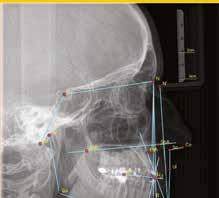

Új dimenzió a CBCT, a fogászati röntgenek és a kefalometriai felvételek diagnosztikájában a MESTERSÉGES

INTELLIGENCIA erejével csak a VIP DENTALBAN!

Dentális státusz elemzése mesterséges intelligencia által CBCT felvételen.

Panorámaröntgen elemzése mesterséges intelligencia által.

Kefalometriai elemzés és pontbejelölés mesterséges intelligencia által.

Legyen az Ön rendelője a fogászati ellátás innovatív központja, és velünk együtt biztosítsa a legmagasabb szintű diagnosztikai szolgáltatást az MI által támogatott elemzésünkkel.